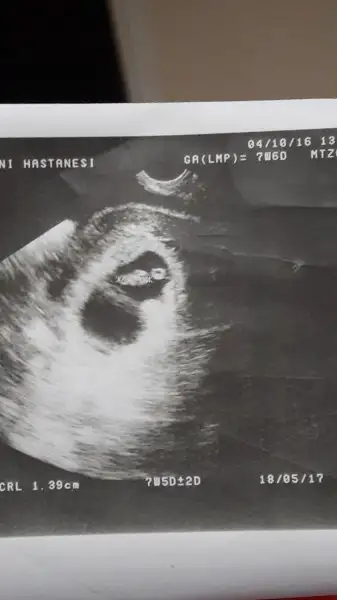

Keseye gore erkek bebisin bence..Havalianne__ Benim ultrason resmime de cinsiyet yorumu yapar misiniz? Vajinal ultrason ve 8 haftalik.Eki Görüntüle 1892583

Havalianne__ Benim ultrason resmime de cinsiyet yorumu yapar misiniz? Vajinal ultrason ve 8 haftalik.Eki Görüntüle 1892583

Eki Görüntüle 1893413 Eki Görüntüle 1893413Havalianne__ cim banada yorum yapar misin? Vajinal ultrason